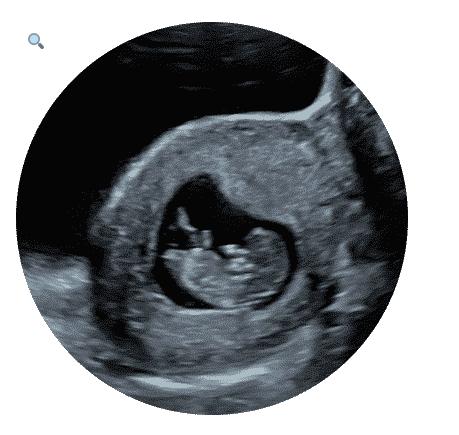

Through this article, learn more about what to avoid during your 4D ultrasound scan at our 4D baby scan clinic in Watford.